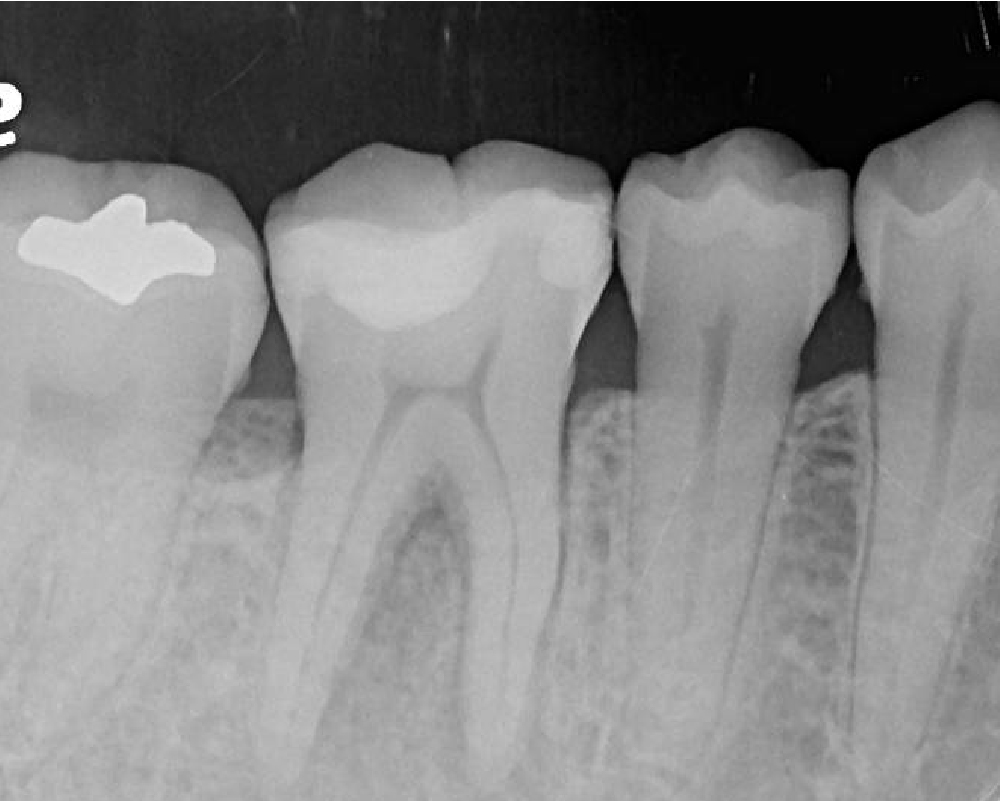

如果缺牙區兩側的牙齒非常健康,為了做牙橋而將健康的琺瑯質磨掉,是非常可惜的。植牙能做到「缺哪裡,補哪裡」,完全不干擾健康的鄰牙。